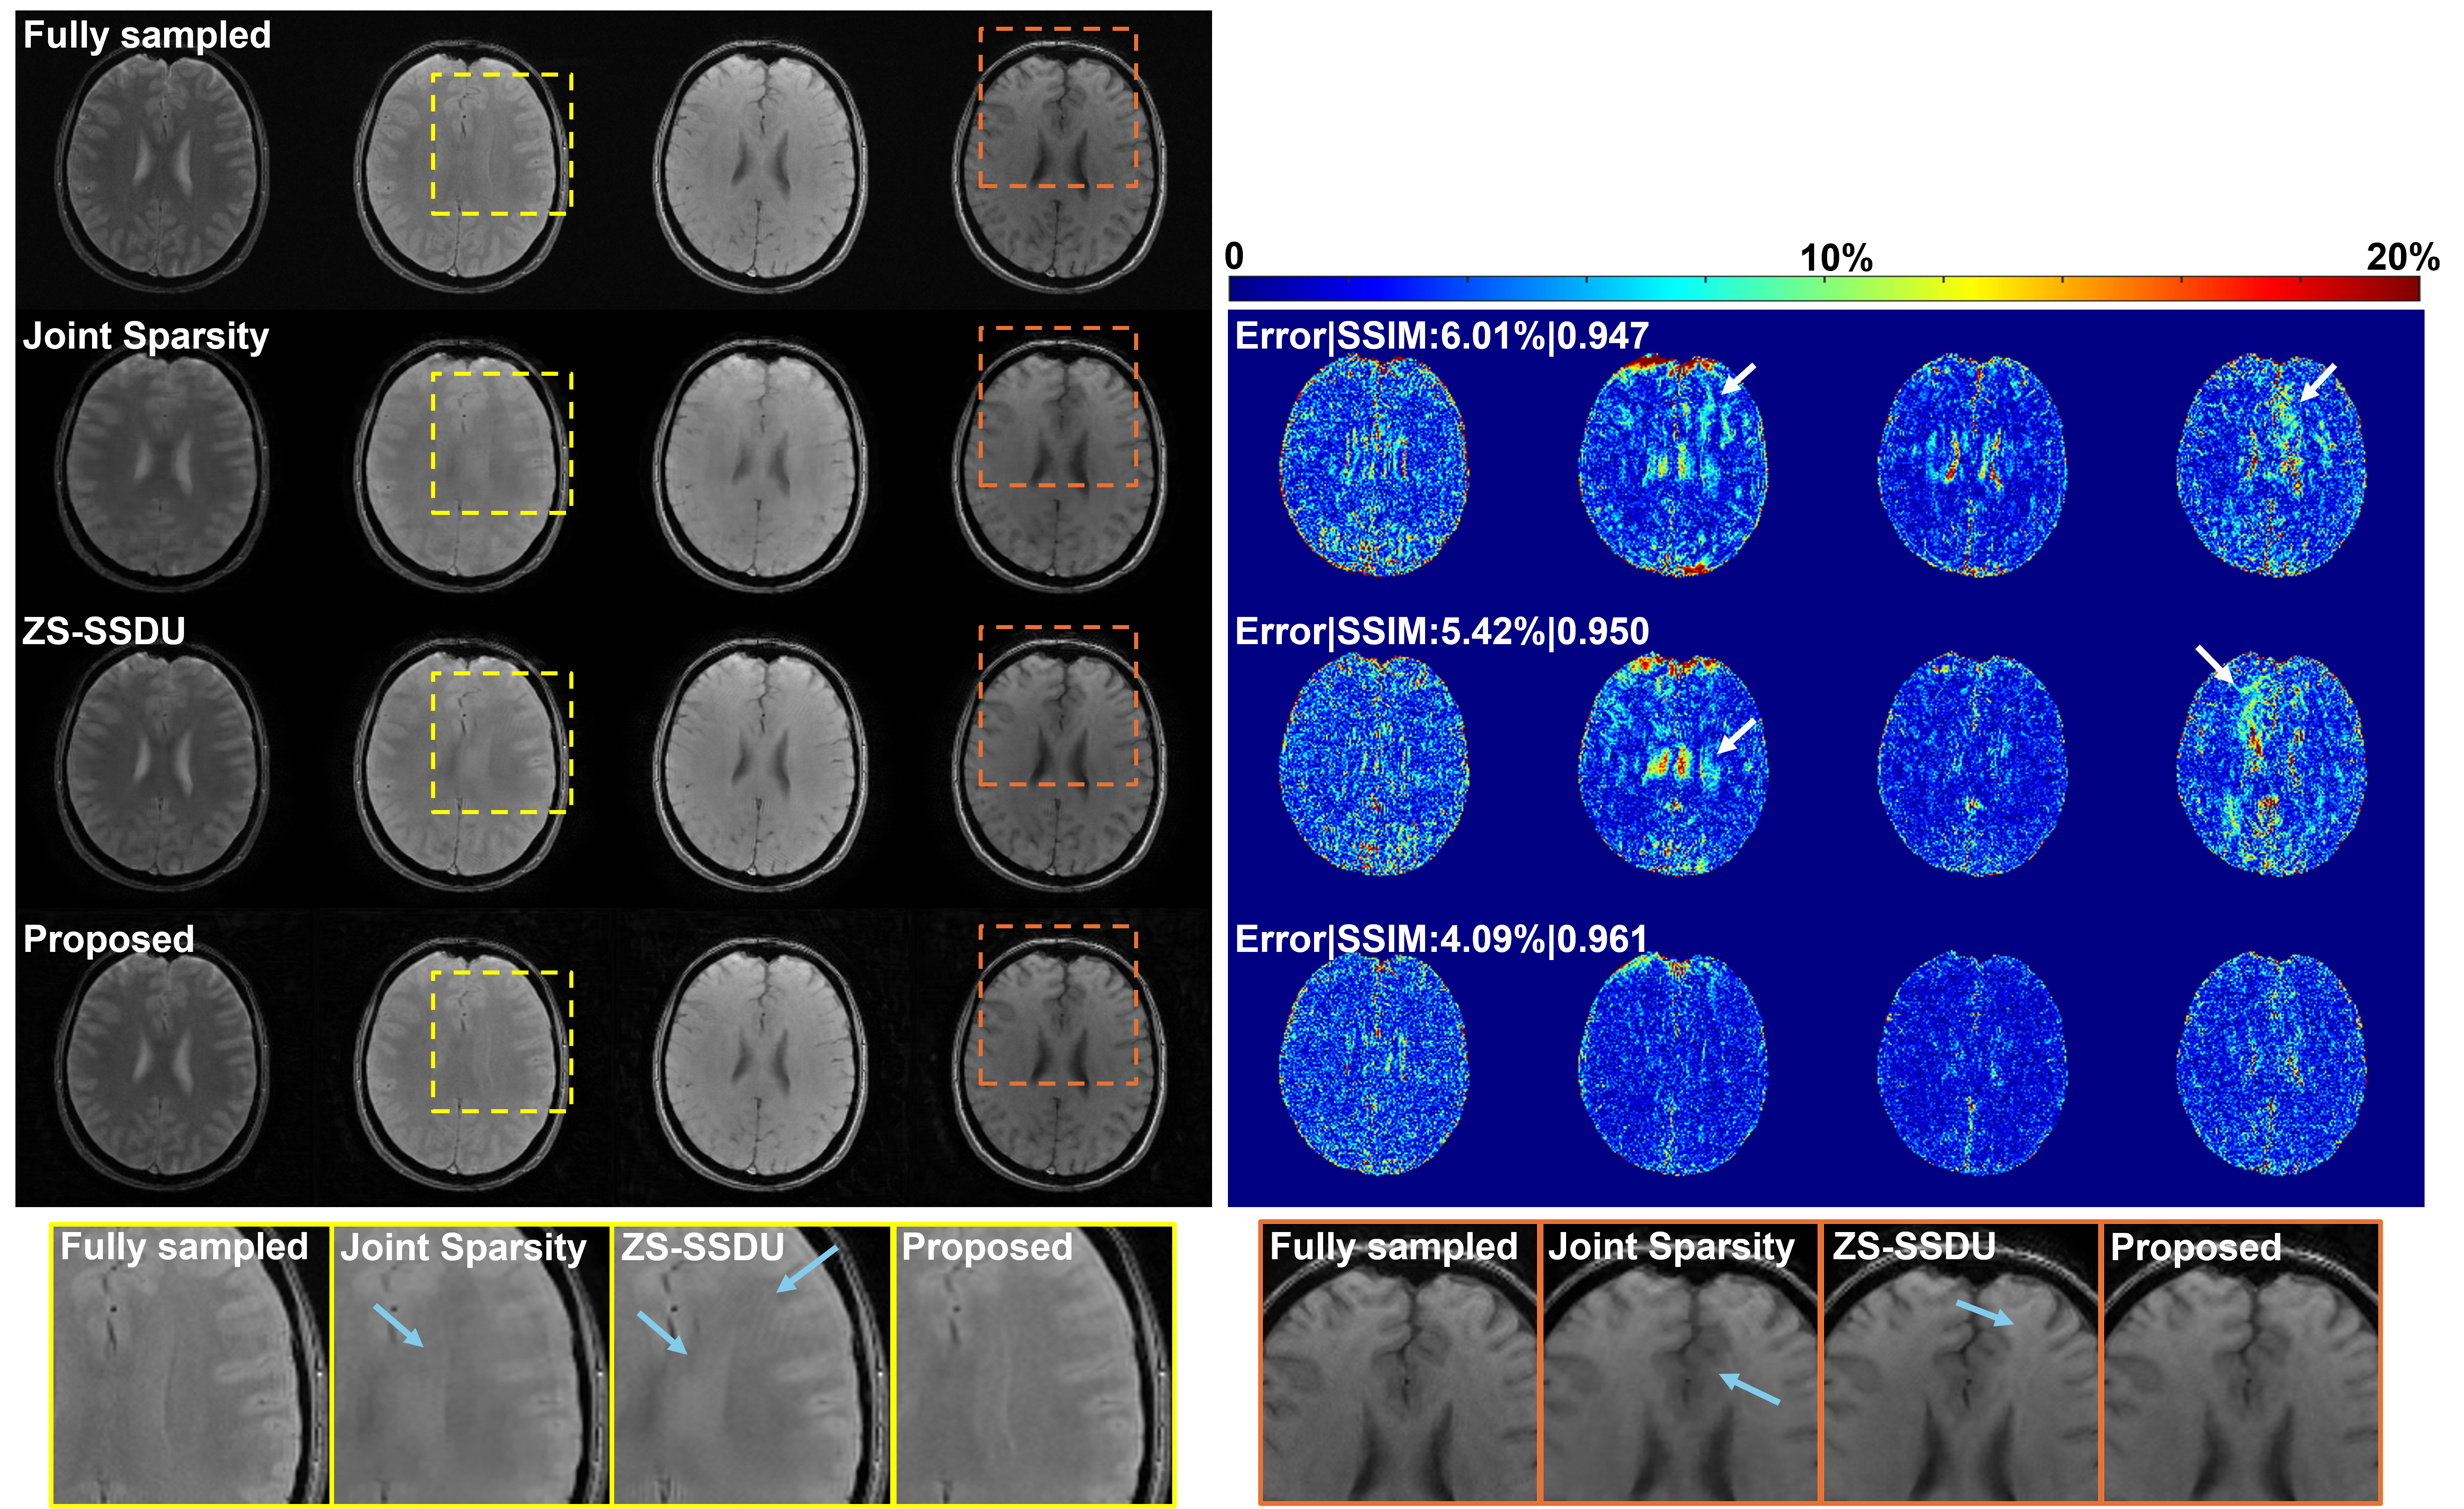

4.3 mapping Results

For mapping, we compared the proposed method with a joint sparsity constrained reconstruction [majumdar2011accelerating] and a state-of-the-art zero-shot self-supervised reconstruction method (ZS-SSDU) [yaman2022zero]. We selected ZS-SSDU as a primary baseline because our method also follows a zero-shot learning paradigm, requiring no supervised re-training or fine-tuning on domain-specific datasets. Representative reconstructed images at AF=6 are shown in Fig. 4. The proposed method consistently produced reconstructions with improved quality and reduced errors across different contrasts (FAs) compared to other methods. The corresponding maps are shown in Fig. 5. The proposed method achieved the most accurate estimates w.r.t. the fully sampled reference as shown by the lowest relative errors and highest SSIM values, effectively suppressing artifacts. The zoomed-in regions further demonstrate a better preservation of structural details by the proposed method. The ZS-SSDU method, although produced lower errors than the joint sparsity method, seemed to result in strong bias in certain localized areas (Fig. 5, last row). These results demonstrated that the proposed representation can work synergistically with zero-shot self-supervised learning, leading to improved reconstruction and quantification performance. More quantitative comparisons under different AFs are shown in Fig. 7.

Fig. 6 compares mapping results estimated from reconstructions produced by different methods at AF = 8. The overall estimation errors and SSIM values w.r.t. the fully sampled data were computed within the brain regions with values lower than ms. The proposed method integrating our disentangled representation and subspace modeling yielded superior performance over a subspace reconstruction method with joint sparsity regularization [zhao2015accelerated] and the ZS-SSDU method. These results also demonstrated the flexibility of the proposed representation to be combined with complementary constraints. Fig. 7 further demonstrates lower reconstruction errors consistently achieved by the proposed method across different AFs.